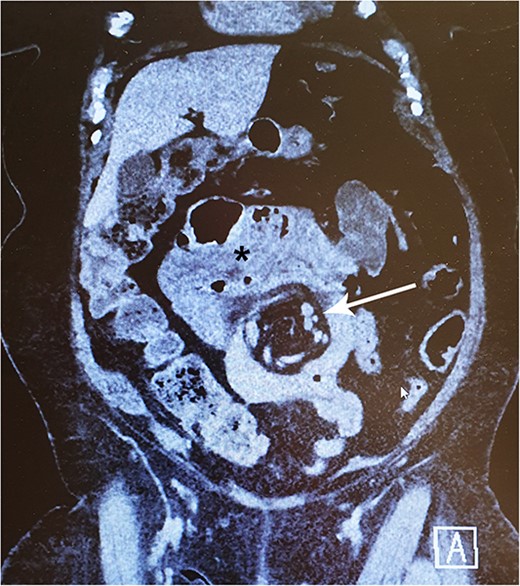

In late 2022, this now 77-year-old patient came to the emergency ward with intense abdominal pain. She had been experiencing transient colicky epigastric pain infrequently for the past few years. At this time, her medical history included hypertension, musculoskeletal disorders, diverticulosis, and a deep vein thrombosis in 2015. She took a daily multivitamin supplement and additional zinc, vitamin C and D, and received vitamin B12 injections every 3 months. A computed tomography (CT) scan revealed a suspicion of IH with a typical swirl sign in the mesenteric vascular structures (Fig. 1). There were no signs of compromised bowel blood perfusion or dilatation in the bowels or stomach. At the time, the exact procedure the patient had undergone 31 years earlier was unclear. The symptoms resolved quickly, and the emergency operation was not necessary. At follow-up, the patient remained symptom-free. Archived medical records revealed that she had undergone a JIB in 1991. In agreement with the patient, we proceeded with exploratory laparoscopy.

A 77-year-old woman with a history of jejunoileal bypass 31 years ago presented with intermittent colicky upper abdominal pain for 1–2 years. A rather painful episode led to hospital admission and CT scan, which showed a mesenteric swirl sign (arrow). Symptoms quickly subsided. Although she remained symptomless after that particular episode, an exploratory laparoscopy converted to laparotomy was performed 5 months later. This revealed a large mesenterial defect under the jejunoileal anastomosis. 390 cm of bypassed small bowel was found to be atrophied and packed with adhesions. This finding may be visible on CT scan (*).

We found no case reports of IH occurring after JIB. Instead, the phenomenon is well-recognized after RYGB and may present with acute onset of colicky epigastric pain, sometimes even radiating to the back, and the symptoms may worsen with eating and be accompanied by vomiting due to bowel obstruction [7, 9]. Nevertheless, the symptoms are often vague and nonspecific, which can make diagnosis challenging and result in delays [11]. The range of consequences of an IH may vary from episodic abdominal pain to bowel strangulation through the defect [7, 12]. A CT scan is helpful in diagnostics but may appear normal in up to 30% of cases and does not exclude the IH [12–14]. The best single finding on a CT scan that suggests IH is a “whirl sign”, in which the mesenteric vessels or fat appear in a swirling pattern [15]. Other suggestive findings include small bowel obstruction or clustered loops, any part of the bowel other than the duodenum behind the superior mesenteric artery, right-sided, or superior to transverse colon location of jejunojejunostomy or mushroom-shaped mesenteric root [14, 15].

In conclusion, it is likely that the patient had an intermittent IH that caused her colicky abdominal pain. This is supported by the presence of a clear mesenteric swirl sign on the CT scan. However, we speculate that the herniation spontaneously resolved during her first hospital admission, which led to the relief of her symptoms. The exact nature of her previous bariatric operation was unclear at the time, as her old medical records were not available. The quick relief of her symptoms during the hospital admission led to the decision to refrain from emergency surgery.